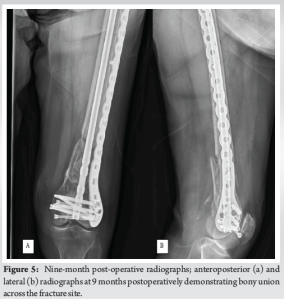

At baseline, she ambulated with a cane. She was made weight-bearing-as-tolerated immediately after surgery. Physical therapy began on post-operative day one. She needed a rolling walker to ambulate but was able to take four steps. She continued to improve her ambulatory status as she walked five feet, six feet with two 90° turn, eight feet, and finally ten feet on post-operative day eight. She was discharged to a rehab facility for further care. At 3 months follow-up, she reported minimal pain and was independently ambulating with a walker (Fig. 4). She was having no difficulty with her activities of daily living. At her most recent 9-month follow-up visit, she was back to ambulating with a cane and subjectively felt better than she did at her 3-month visit. She had no tenderness to palpation and had no pain with prolonged walking or other activities of daily living. Her X-rays demonstrated union at the fracture site with consolidation of her callus on three out of four cortices (Fig. 5a and b). She had returned to her baseline level before surgery with her reported short musculoskeletal functional assessment (SMFA) at 9 months (81) equivalent to her baseline pre-injury SMFA (81).